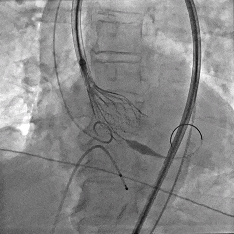

缓慢脱钩

瓣膜无位移

脱钩后造影

瓣膜位置可,无瓣周漏

左冠切线造影,瓣膜同轴性佳,位置可,无瓣周漏

术中最关键环节在于瓣膜的精准定位与稳定释放。ScienCrown瓣膜系统的“全释放/全回收”功能,允许术者在最终释放前,更充分地评估调整瓣膜的定位与稳定性,极大提升手术容错率与安全性。